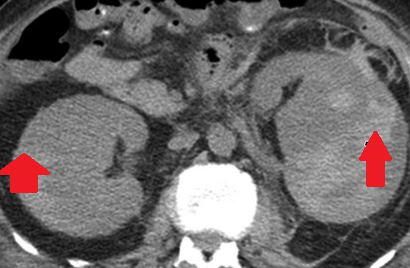

Αμφοτερόπλευρη αυτόματη νεφρική αιμορραγία — κοκκιωμάτωση Wegener (Ευγενική παραχώρηση Dr. V. Penopoulos)